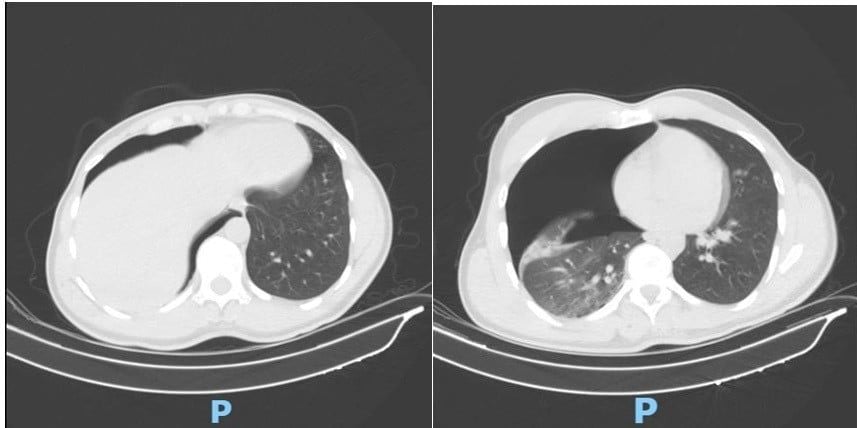

Phim CT scan lồng ngực sáng ngày nhập viện ghi nhận tràn khí màng phổi phải lượng nhiều. Ảnh: BV

Ngay khi nhập viện, bệnh nhân O.G được chụp CT scan lồng ngực - mạch máu khẩn cấp. Kết quả ghi nhận tràn khí màng phổi phải lượng nhiều gây chèn ép phổi; gãy cung bên xương sườn 2, 3, 4 phải; gãy phức tạp 1/3 giữa xương đòn phải, di lệch nhiều, có mảnh rời.